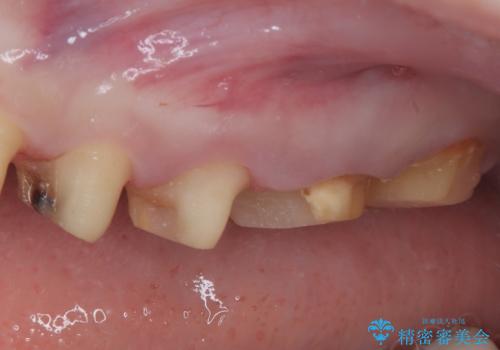

- かかりつけ医にて歯周病治療の名目で治療を行っていたものの、治療プランが明確でないままにインプラント処置を行うとことに疑問を感じ、来院された患者様です。

かかりつけ医では、歯周病治療は終了したため、抜歯を行った右上奥歯にインプラント埋入を行うとの案内があったそうです。

検査を行ったところ、歯周外科処置や抜歯が必要と思われる箇所が散見されたため、あらためて当院に歯周病の初期治療から行うこととしました。

下顎前歯の叢生も気になっており、矯正治療も並行して進めていくこととしました。